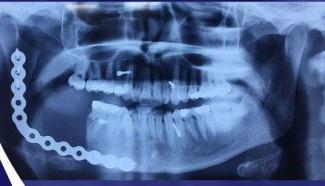

به گزارش خبرنگار طاووس بهشت؛ تیم درمانی دانشگاه علوم پزشکی کاشان موفق به عمل جراحی و درمان کامل بیمار جوان ۲۳ساله ی آران و بیدگلی مبتلا به giant cell tumor فک پایین در کاشان شدند.  این عمل جراحی و درمان بعد از آن در نوع خود کم نظیر است و بیشتر در مراکز درمانی واقع در مرکز استا نها انجام میشود که برای اولین بار توسط تیم جراحی دکتر امیر سالار سید یاحسین عضو هیئت علمی دانشگاه کاشان انجام گرفت. انتهای پیام/ فاطمه بی خوابی آرانی